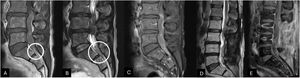

A Gadolinium-enhanced lumbar spine MRI was performed. MRI showed an irregularly shaped intradural lesion extending from L3 to L5 with a maximum length of 4.5 cm. The lesion exhibited a medium signal on T1 and hypointense on T2-weighted imaging with peripheral and irregular enhancement. A particular finding at the bottom of the thecal sac suggested subarachnoid hemorrhage according to a slightly hyperintense level on T1 and low-signal level on T2-weighted imaging corresponding to subacute bleed (Fig. 1). Spinal vascular malformation was considered as a differential diagnosis, but spinal digital subtraction angiography showed no evidence. A complete spinal MRI was performed excluding the presence of other tumors. The treatment decision was surgical resection with intraoperative neurophysiological monitoring (IONM).

Lumbar spine MRI sagittal view, T1 and T2-weighted (panel A, B) exhibiting an intradural lesion from L3 to L5 appearing isointense to CSF on T1 and hypointense on T2. On the bottom of the thecal sac, a slight hyperintense on T1 and low signal level on T2-weighted suggested subacute subarachnoid bleeding (White circle). The gadolinium-enhanced T1-weighted sagittal view (panel C) shows a peripheral enhancement of the intradural lesion.

The 8-month postoperative lumbar spine T2 and gadolinium-enhanced T1-weighted MRI sagittal views exhibited surgical and radiation therapy inflammatory changes without tumor recurrence (panels D and E).